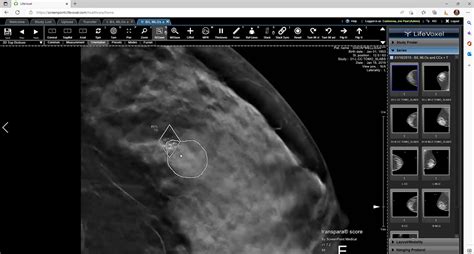

When it comes to breast cancer detection , the traditional approach has been the cornerstone of our efforts for decades. Mammography , for instance, has been the go-to method for screening, and it has undoubtedly saved many lives by catching tumors that might otherwise go unnoticed. However, despite its established role, it’s not without its limitations and challenges, and understanding these is key to appreciating why new technologies like deep learning are so desperately needed. Think about it, guys: traditional mammograms can be uncomfortable, and sometimes, they don’t give a clear picture, especially for women with dense breast tissue. This can lead to what we call false positives , where a woman is told there might be an issue, causing immense stress and anxiety, only for further tests to reveal it was nothing. On the flip side, we also face the challenge of false negatives , where a small, insidious tumor is missed, potentially delaying crucial treatment. These aren’t just statistics; these are real people, real fears, and real missed opportunities for early detection .

Beyond the technical aspects of the imaging itself, there’s also the human element. Radiologists , who are truly incredible medical professionals, spend countless hours poring over these images, looking for subtle signs of abnormality. It’s a highly skilled, incredibly demanding job that requires immense concentration and expertise. But let’s be honest, even the most experienced human eye can get tired, or miss something tiny in a vast sea of data. The sheer volume of mammograms to be reviewed is staggering, and the workload on radiologists is constantly increasing. This can lead to variability in interpretations, where two different radiologists might come to slightly different conclusions, or a radiologist might miss a nuanced detail that, in retrospect, was indicative of cancer. This isn’t a criticism of our amazing healthcare providers; it’s just the reality of relying solely on human interpretation for such a critical task. The goal isn’t to replace these experts but to equip them with advanced tools that can act as a powerful second pair of eyes, enhancing their capabilities and ensuring greater consistency and accuracy in breast cancer detection . This is precisely where the promise of deep learning shines through, offering a revolutionary way to support and augment current screening practices, aiming to reduce both false positives and false negatives, and ultimately, improve patient outcomes. The challenges of the traditional path highlight the urgent need for innovative solutions, and AI is stepping up to the plate in a big way.